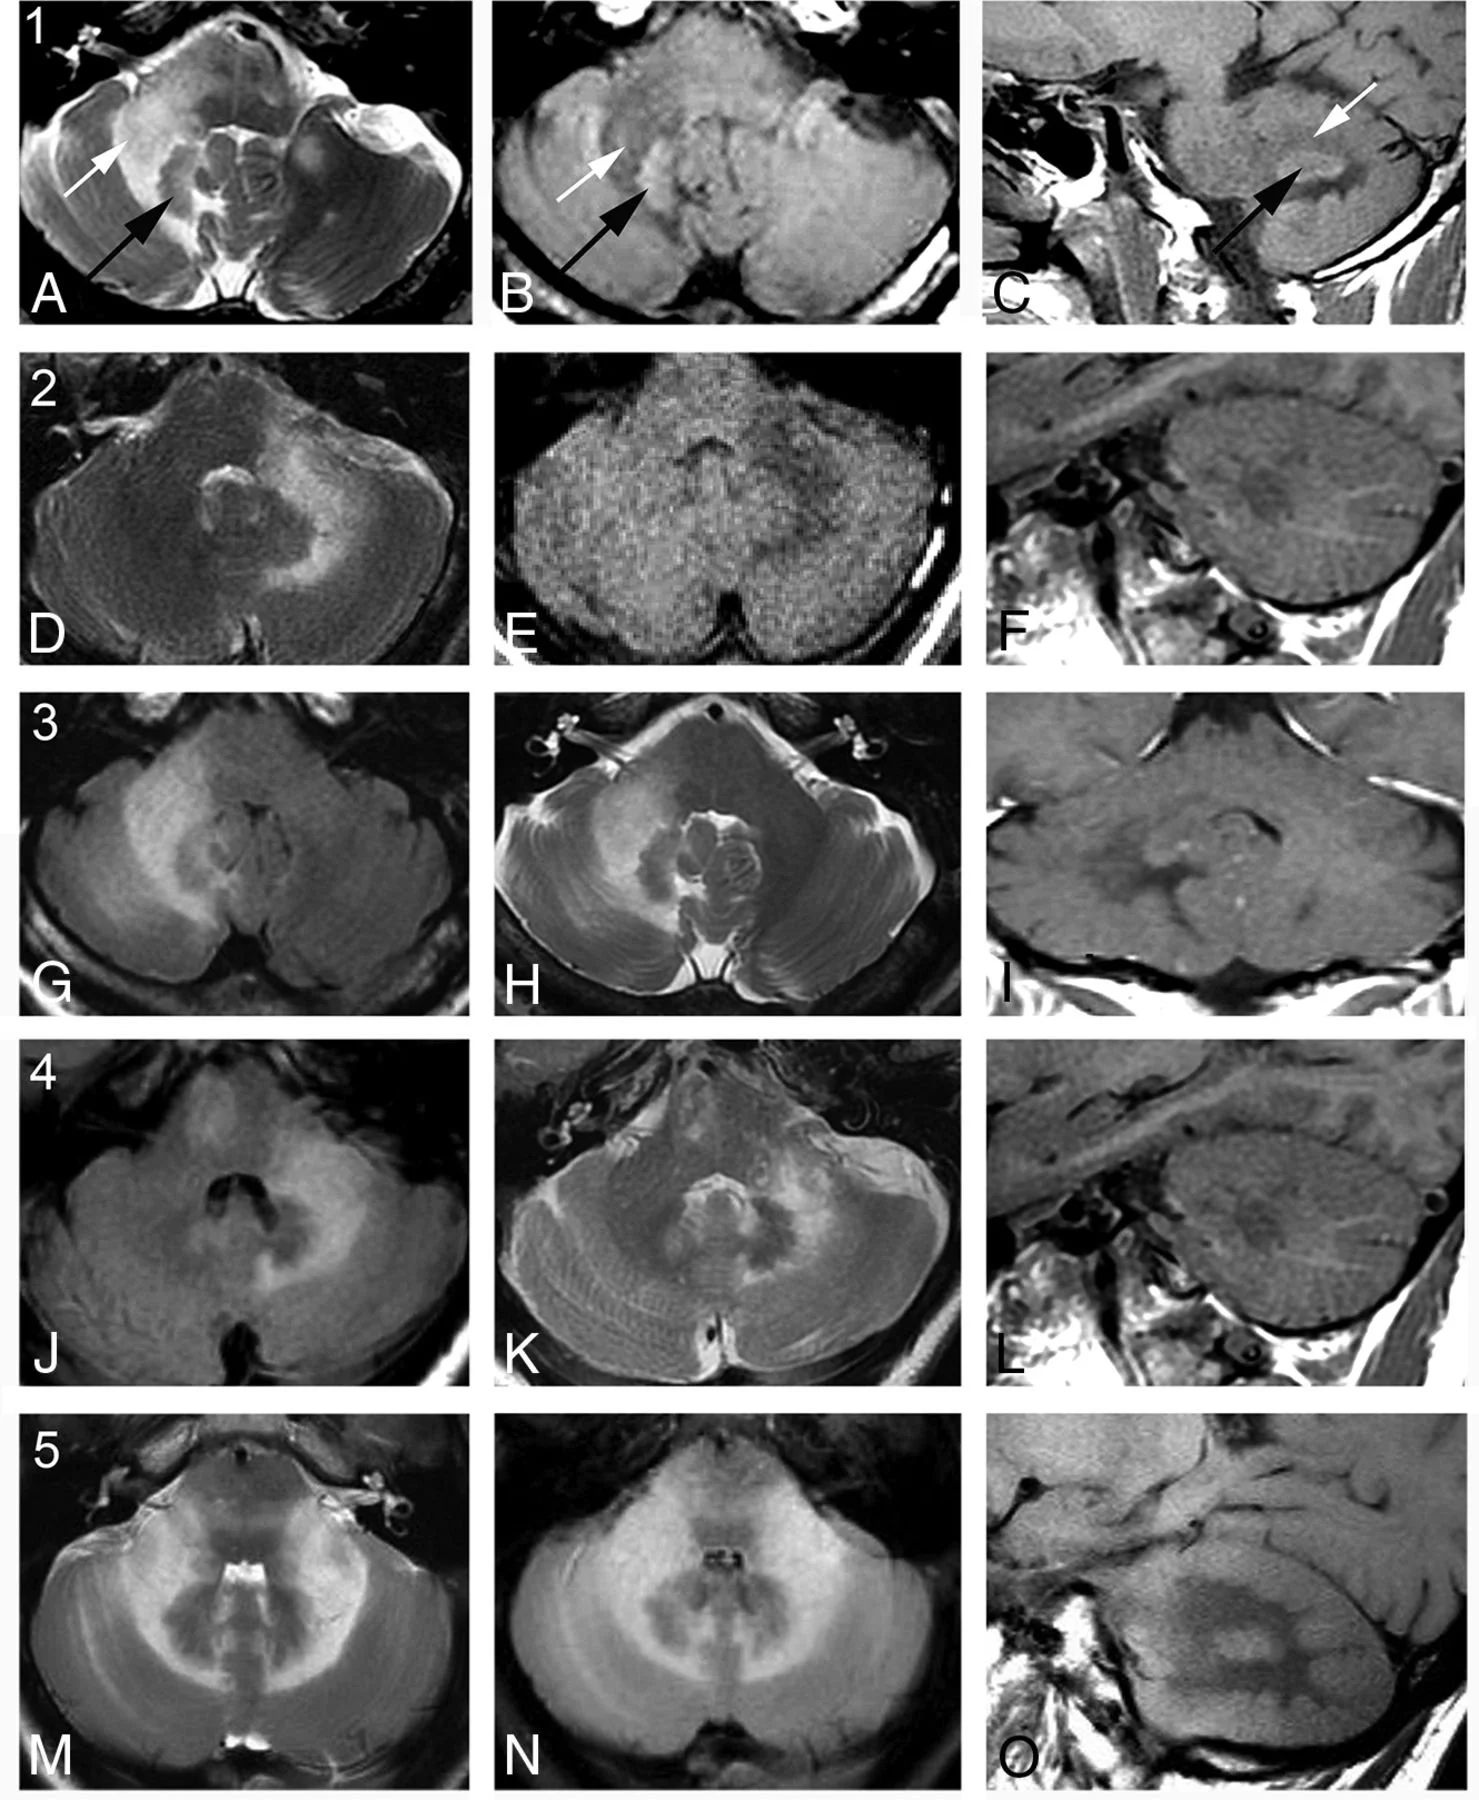

• Shrimp sign - T2 hyperintensity of the cerebellar white matter but which spares the dentate nucleus

Image showing abnormally hyperintense dentate nuclei.

Note: This image is not PML it just shows anatomy of dentate nuclei well since they are so abnormally bright here,

• N. Adra, A.E. Goodheart, O. Rapalino, P. Caruso, S.S. Mukerji, R.G. González, N. Venna, J.D. Schmahmann, MRI Shrimp Sign in Cerebellar Progressive Multifocal Leukoencephalopathy: Description and Validation of a Novel Observation American Journal of Neuroradiology May 2021, DOI: 10.3174/ajnr.A7145 (PML shrimp)

• K.M. Bond, W. Brinjikji, L.J. Eckel, D.F. Kallmes, R.J. McDonald, C.M. Carr, Dentate Update: Imaging Features of Entities That Affect the Dentate Nucleus, American Journal of Neuroradiology Aug 2017, 38 (8) 1467-1474; DOI: 10.3174/ajnr.A5138 (dentate nuclei)